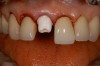

Figure 15 – Extraction of anterior tooth No. 8 without detaching the gingiva.

Figure 15

Figure 16 – Extracted tooth with the root canal material (gutta percha) extending from the apex

Figure 16

Figure 17– A zircon (white) abutment was attached immediately after extraction and implant placement.

Figure 17

Figure 18 – Immediate placement of temporary crown over the abutment; laser crown lengthening was performed on the adjacent teeth to improve gingival symmetry

Figure 18

Figure 19 – Four months after surgery with temporary crown over the implant at No. 8.

Figure 19

A dental implant most closely replicates natural tooth structure. Once it is osseointegrated, many patients cannot differentiate an implant from a natural tooth. Furthermore, dental implants do not decay or need root canal therapy. Even though the cost is slightly more than a bridge, it is an investment for the future, as implants usually last longer than a bridge. A 10-year report on posterior single implants shows a success rate of 97%.33 Once an implant is placed, the osseointegration and tissue healing time of approximately 4 months is necessary before a final crown is placed. A temporary crown can be placed the same day the implant is placed, but this is only for esthetics, not for function (Figure 15 through Figure 19).